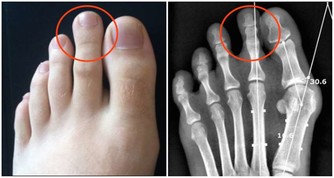

兒童期超重、肥胖會增加高血壓、糖尿病、高甘油三酯、代謝綜合徵等的發生風險,

肥胖還會影響兒童青春期發育,危害呼吸系統及骨骼,甚至對心理、行為、認知及智力產生不良影響。